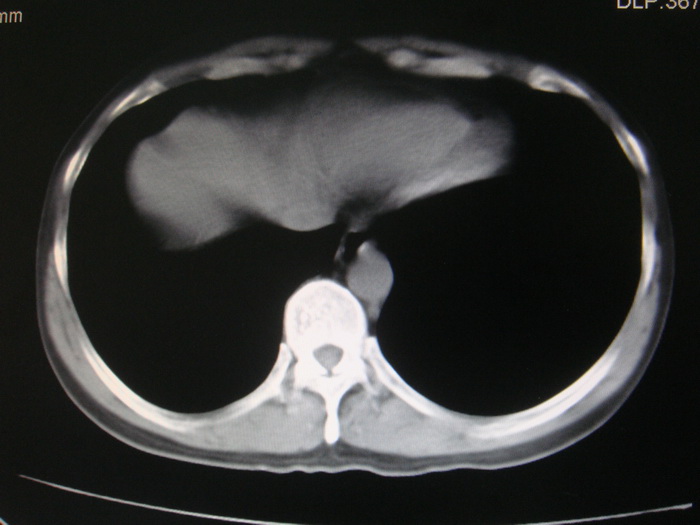

标题: CT28366:男性,45岁,偶尔发现右颈部肿块行胸部CT扫描。 [打印本页]

男性,45岁,偶尔发现右颈部肿块行胸部ct扫描。

两肺多发结节灶及纵膈淋巴结肿大考虑为转移

两肺多发性转移瘤,纵隔淋巴结转移。

两肺多发性转移瘤,纵隔淋巴结转移。食道中上段管壁似乎增厚,作相关检查。

两肺多发性转移瘤,纵隔淋巴结转移瘤。